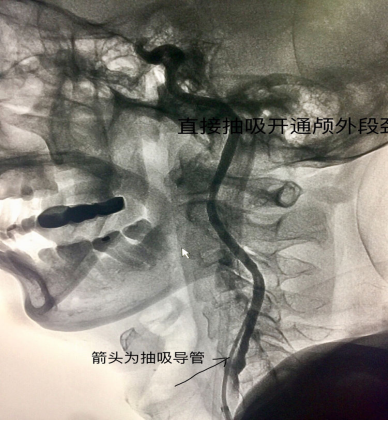

应用中间导管直接抽吸颈内动脉岩骨段

海绵窦以下颈内动脉打通

虽然血管己开通,但可见颈动脉分叉部血栓影,血栓下方可见中间导管头,上第二武器支架吧!